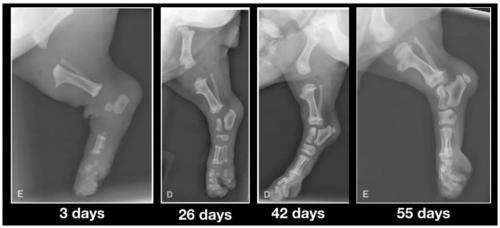

Was prägt Welpen fürs Leben? Was bedeutet Prägung überhaupt? Wenn Sie das Wort „Prägung“ mal im Internet eingeben werden Sie feststellen, dass es verschiedenste Definitionen gibt. Im Zusammenhang mit der Hundehaltung spricht man eher von „prägeähnlichen Lernprozessen“. Dies liegt daran, dass im wissenschaftlichen Sinne Prägung ein unumstößlicher Lernvorgang ist. Hunde jedoch können ihr Verhalten verändern und daher ist einmal Erlerntes keineswegs irreversibel. Um es nicht unnötig kompliziert zu machen, lassen wir die Wissenschaft außen vor und nennen den Begriff nachfolgend dennoch Prägung. Die Neonatale- und Übergangsphase Jeder Züchter und jeder Welpenbesitzer legt größten Wert darauf, seinen Welpen bestens aufs Leben vorzubereiten. Von Geburt an ist es für den Welpen wichtig, dass er durch sein genetisch fixiertes Verhalten positive und negative Erfahrungen macht. Welpen können trotz verschlossener Ohrkanäle Schreckreaktionen auf laute Geräusche zeigen, warm und kalt unterscheiden und auch Schmerzreaktionen zeigen. Milder Stress ist hier das Zauberwort. Dieser fördert das Immunsystem und befähigt den Organismus mit Stress und Belastung umzugehen. Zum Ende der 3. Lebenswoche bekommen Umweltreize eine Bedeutung für den Welpen. Seine Motorik wird kontrollierter und die Schlafperioden werden kürzer. Die Sozialisationsphase beginnt In dieser Phase finden wichtige Wachstums- und Differenzierungsprozesse im Gehirn statt und sorgen so dafür, dass sich die Neuronen im Gehirn untereinander vernetzen und der Welpe somit besser lernen kann. Ganz besonders wichtig ist es in dieser Phase, ihn weder in Watte zu packen noch zu überfordern. Bieten Sie ihm die Möglichkeit Kinder, ältere Menschen und Erwachsene kennen zu lernen oder auch Erfahrungen im Garten zu sammeln. Besonders sollten Sie in dieser Phase darauf achten, dass der Welpe sich selbstständig in verschiedenen Situationen bewegen und darf. Der Welpe soll eigenständig lernen… Demutsgesten zu zeigen, mit Angst fertig zu werden, seine Zähne dosiert einzusetzen, Aggressionen und Frustrationen abzubauen, und nach Lösungen zu suchen. Der Welpe muss lernen, sein Verhalten der Situation anzupassen Nicht alles im Leben läuft so, wie er es wünscht und deswegen geht die Welt nicht unter. Diese Lernvorgänge sind für ihn äußerst wichtig, um im späteren Leben seine Reaktionen dem Kontext anpassen zu können. Der kleine Kampf mit seinen Geschwistern an der Futterschüssel, ist für diesen Lernprozess zum Beispiel sehr zuträglich. Ein ständig reichhaltiges Futterangebot würde den Lernprozess unterbrechen. Züchter und Welpenbesitzer müssen die Prägung fortsetzen Studien belegen, dass Welpen die sowohl beim Züchter als auch beim künftigen Welpenbesitzer betont ruhig aufwachsen, später die gelasseneren Hunde sind. Viele bekommen plötzlich wahnsinnigen Stress Auf einmal denken Sie an die Sozialisationsphase und meinen, sie müssten noch so viel erledigen. Der Welpe soll Busfahren, die Stadt kennenlernen, jegliche Menschen und Tiere in der Nachbarschaft erleben und und und… All dies kann einen Welpen ganz schön überfordern Wir sollten unsere Ansprüche wirklich umsichtig dem einzelnen Welpen und der zukünftigen Lebenssituation anpassen. Wer bekommt den Welpen? Welche Ansprüche haben Sie? Möchten Sie einen ruhigen oder agilen Hund? Dementsprechend sollte auch seine Förderung angepasst sein. Wenn Züchter sich zu starke Mühe geben und dem Welpen alle Umweltsituationen aussetzen wollen, wird ihn später wenig beeindrucken. Der Mittelweg ist auch hier wieder ideal. Nehmen Sie sich Zeit Bei all dem Freizeitstress, dem Welpen häufig ausgesetzt sind, wird eines gerne vergessen: Welpe und Familie müssen sich kennen lernen, um eine Bindung zueinander aufbauen zu können. Dazu sind die alltäglichen Situationen in der Regel für alle Beteiligten schon Herausforderung genug. Welpengruppen, Café und was es sonst noch so gibt, sollte da zunächst nebensächlich sein. Nur Sie und Ihr Welpe zählen und seien Sie gewiss: Ihr Welpe wird auch später noch lernen können Bus zu fahren. Sorgen Sie zunächst für eine gute Mensch-Hund –Beziehung. Wenn das stimmt, dann kann die Erziehung anfangen. Das A und O der Bindung Hundehalter verstehen unter Bindung Unterschiedliches. Während die Einen Bindung mit Erziehung verwechseln, verstehen die Anderen darunter, dass der Hund die Nähe seines Menschen sucht. Doch Bindung ist viel mehr als das. Bindung ist ein unsichtbares Band Egal ob in der Tierwelt oder bei uns Menschen: Schon die Kleinsten lernen, sich zu binden, wobei man Bindung keinesfalls mit Abhängigkeit verwechseln darf. Die kindliche Abhängigkeit nimmt im Laufe des Lebens ab, wobei die Bindung ein Leben lang bestehen kann. Warum binden sich Lebewesen? In der Tierwelt dient Bindung schlichtweg dem Überleben. Gemeinsam ist man stark und daher kommen als Bindungspartner ausschließlich Jene in Frage, die man gut kennt und auf die man sich verlassen kann. Genau wie wir Menschen, suchen auch Hunde nach Sicherheit und Geborgenheit. Wissenschaftler haben heraus gefunden, dass diese ähnlichen Bedürfnisse, die vertrauensvolle und tiefe Bindung zwischen Mensch und Hund erklären. Hat Bindung etwas mit Nahrung zu tun? Absolut nicht. Zwar schätzen unsere geliebten Vierbeiner Hundekekse sehr, jedoch sind sie nicht verantwortlich für eine tiefe Bindung. Vielmehr ist die Sicherheit, Geborgenheit und Akzeptanz wichtig für eine gute Bindung. Das erklärt auch, warum sowohl Hund als auch Kind in einer Gefahrensituation sofort zur Mutter oder zum Hundebesitzer laufen. Wie erreichen Sie eine gute Bindung zu Ihrem Hund? Fühlt ihr Hund sich unsicher oder hat er sogar Angst, wird er versuchen durch fiepen, bellen, heulen, lecken, anstubsen, Körper- oder Blickkontakt Nähe zu Ihnen herzustellen. Reagieren Sie auf diese Zeichen angemessen und selbstsicher. Sofort wird ihr Hund sich sehr viel besser fühlen. Verletzt sich Ihr Tier, reagieren Sie sofort, um ihm zu helfen. Beantworten Sie seine Zeichen, wie zum Beispiel Blickkontakt, stets mit einem freundlichen Wort. Zeigen Sie Ihrem Hund, dass Sie ihn wahrnehmen und schätzen. Seien Sie feinfühlig und dies immer, dann können Sie ein unsichtbares Band aufbauen, welches ein Leben lang erhalten bleibt. Welche Fehler kann man machen? Verwechseln Sie Bindung nicht mit Erziehung! In der Erziehung ist es die wohlgemeinte Konsequenz, die ans Ziel führt. Bei der Bindung ist es das Gefühl und Ihre Feinfühligkeit, was Sie verbindet. Reagieren Sie stets angemessen auf das Verhalten Ihres Hundes. Droht Gefahr schreiten Sie ein, aber lassen Sie sich zum Beispiel im Restaurant nicht von bettelnden Gesten beeindrucken. Dies betrifft nicht die Bindung, sondern ganz klar die Erziehung. Würden Sie in der Situation auf Ihren Hund eingehen oder gar ihm nachgeben, dann hat er sicherlich eines gelernt: Dass sein Verhalten erfolgreich war. Aber die Bindung bleibt davon unberührt. Fazit: Jeder schätze sich glücklich, den eine tiefe Bindung zu seinem Hund verbindet. Arbeiten Sie ein Leben lang daran. Dies lohnt sich, denn Sie werden reichlich dafür beschenkt. Wieviel Bewegung braucht ein Welpe ?? Golden Retriever Welpen befinden sich in den ersten 18. Monaten in einem Stadium der Knochenentwicklung. In dieser Zeit sind die Knochen sehr empfindlich, da sie noch weich sind dadurch nur wenig belastet werden sollten. Es gibt einige Punkte, die man unbedingt einhalten sollte: Absolutes Treppen-Verbot, tragen sie ihren Welpen also so lange es geht die Treppen auf und ab. Der Welpe muß unbedingt Ruhepausen mache, fordern sie ihn niemals zum Spielen auf, wenn er gerade schläft Vermeiden sie extreme Bewegungen, dazu gehören Spurts mit schnellen Stop Niemals an den Beinen oder der Rute ziehen Lassen sie den Welpen über keine Hindernisse springen - kein Agility bevor er 18. Monate alt ist. Beiss-Reiss Spiele vermeiden, sie können zur Gebißverformung führen Keine Fahrradtouren bevor der Hund ausgewachsen ist. Lassen sie ihn lieber auf einem Feld oder Wiese toben, der weiche Boden tut den Gelenken gut, auch Traben ist besser als Galoppsprünge. 5-Minuten Regel ein Welpe soll täglich nur 5 Minuten je Lebensmonat Bewegung haben. Körperliche Überanstrengung in Kombination mit hochkalorienhaltiger Fütterung führt neben dem genetischem Aspekt oft zu Gelenkerkrankungen wie HD/ED. Bewegen Sie im ersten Lebensjahr ihren Welpen lieber zu wenig als zu viel. Passen Sie das Tempo der Gassirunde an - ein strammer 20-minütiger Weg kann schon zu viel sein !